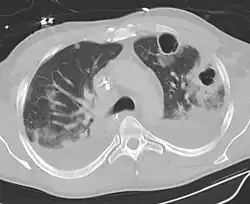

Bei besonderen Fragestellungen und schweren Verläufen können folgende Untersuchungen hinzukommen:

- Ultraschall des Pleuraspalts zum Nachweis eines Pleuraergusses und eines pleuranahen Infiltrats

- Computertomografie der Lunge

Beim Verdacht auf eine Pneumonie werden in der Regel zwei Röntgenbilder der Lunge angefertigt. Im Röntgenbild stellen sich schlecht belüftete Areale hell dar. Diese können z. B. auf eine Lungenentzündung hindeuten. Diese Veränderung (Infiltrat) entsteht durch die Einwanderung von Leukozyten (Infiltration) und die entzündlich bedingte Schwellung. Sind die luftleitenden Teile der Lunge und die Lungenbläschen nicht betroffen – wie bei einer interstitiellen Pneumonie (Entzündung des Bindegewebes zwischen den Lungenbläschen) –, stellen sie sich im Röntgenbild dar (positives Bronchopneumogramm). Sind hingegen die Lungenbläschen in dem entzündeten Bereich nicht mehr zu sehen, deutet dies darauf hin, dass sich dort Flüssigkeit befindet und die Entzündung in den Lungenbläschen stattfindet wie z. B. bei einer Lobärpneumonie.